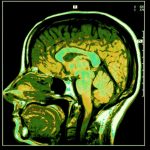

The term glioma refers to certain tumors that originate from the brain. A third of brain tumors are gliomas, and they start from the glial cells around the brain. These include astrocytes, oligodendrocytes, and ependymal cells. The tumors are called intra-axial brain tumors, as they grow within the substance of the brain and mix with normal brain cells.

One type of glioma, called the oligoastrocytoma, is composed of more than one kind of glial cell; thus, some refer to it as mixed gliomas. In mixed glioma, oligodendrocytes and astrocyte rapidly increase, forming a mass.

The tumors are often found in the cerebellum are common in adult men.